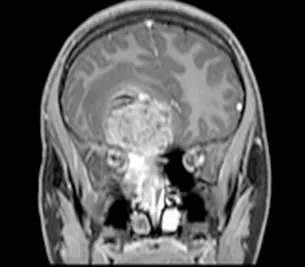

一名15岁、既往健康的男性,因额部头痛加剧、恶心、呕吐和疲劳两周病史就诊。家属注意到在就诊前一个月出现言语失控和非典型行为。他的神经系统检查显示双侧视乳头水肿,无其他局灶性缺损。所有血液检查均正常,血清生殖细胞肿瘤标志物也为阴性。脑和鼻旁窦的计算机断层扫描(CT)和磁共振成像(MRI)扫描显示,右侧有一个5.5 x 4.4 x 5.6厘米的肿块,起源于鼻腔、筛窦和蝶窦。它已侵蚀筛板进入前颅窝。该肿块在CT扫描上未钙化(图1),与脑组织等密度,伴有不均匀的对比增强。该肿块在T1和T2加权MR图像上(图2、3、4)与脑组织等信号,并在钆增强后显示不均匀强化。注意到周围有血管源性脑水肿和占位效应。脊柱MRI未见转移证据。

图2:冠状位T1加权钆增强MRI扫描,证实了起源于鼻腔并延伸至前颅窝的大肿瘤团块的发现。对额叶下部的占位效应和轻微的中线移位是明显的。

图4:冠状位T2加权MRI扫描,证实了颅内肿瘤成分的不均匀实性和囊性性质。病灶周围水肿以及肿瘤相关的中线移位也清晰可见。